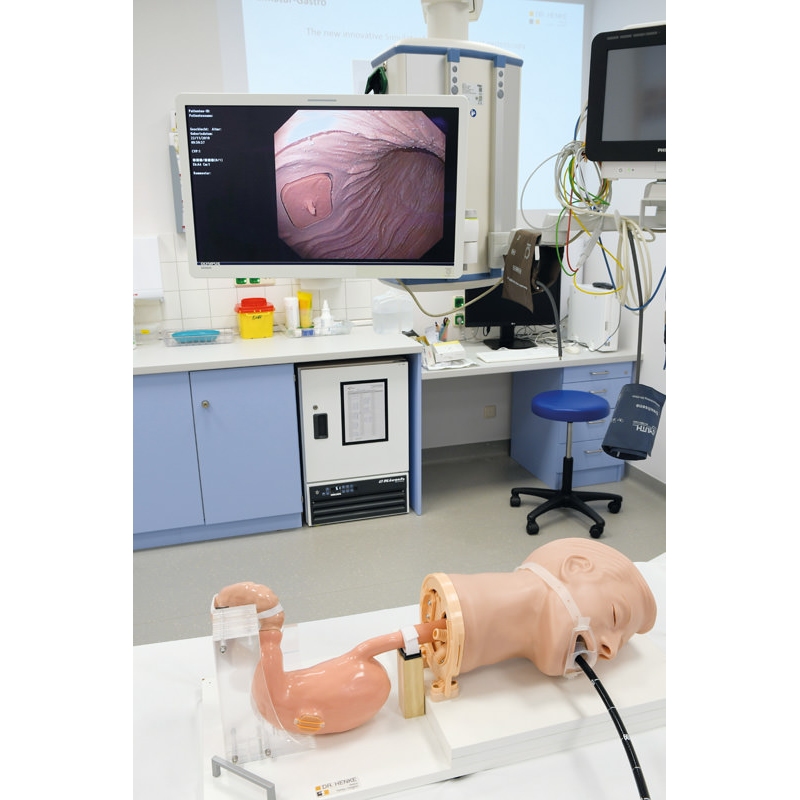

Simulator Gastro združuje možnosti realističnega anatomskega modela in usposabljanja za intervencijsko endoskopijo. Veliko število različnih vložkov omogoča zdravljenje polipov, kot so vbrizgavanje, dvigovanje, rezanje in odstranjevanje, simulacija zaustavitve krvavitve, stentiranje in drugo. Simulator in vložki so izdelani iz popolnoma umetnega materiala.

- Model za usposabljanje za intervencijsko gastroskopijo

- Vadba z obstoječimi endoskopi in originalnimi pripomočki